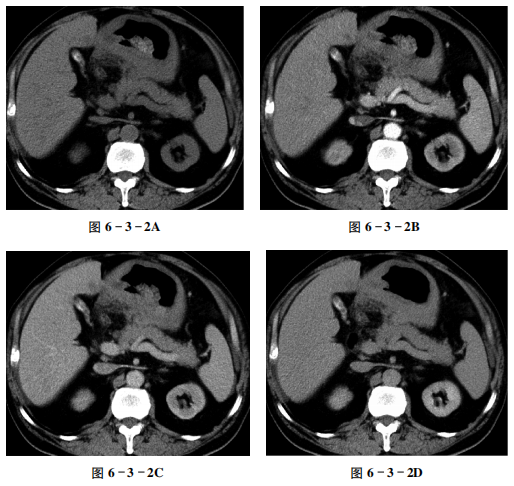

【病史摘要】 男性,72岁。上腹部隐痛1个月余。

【CT征象】 平扫示胆囊体积缩小,胆囊壁增厚、毛糙,胆囊腔内见环形高密度影(图6-3-2A)。

增强扫描胆囊壁及胆囊腔内病灶未见明显强化征象(图6-3-2B~D)。

【重要征象】 胆囊缩小伴囊壁均匀性增厚。

【CT拟诊】 ①慢性胆囊炎伴胆囊结石。②胆囊息肉。③胆囊腺肌症。④胆囊癌。

【病理诊断】慢性胆囊炎。